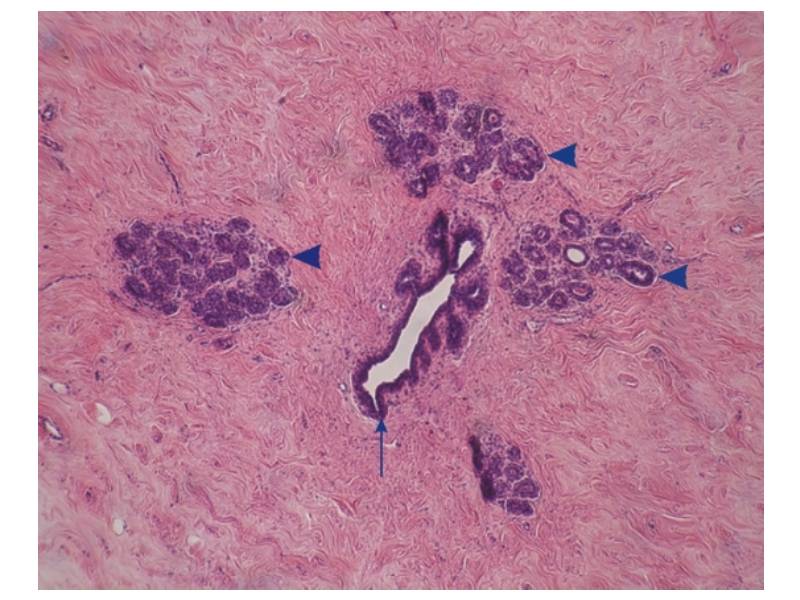

Mammary gland and digestive track

Histology